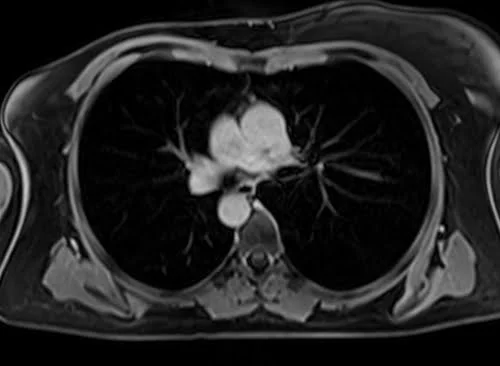

VIBE FAT SAT AXIAL POST CONTRAST SEQUENCE USED IN CHEST IMAGING